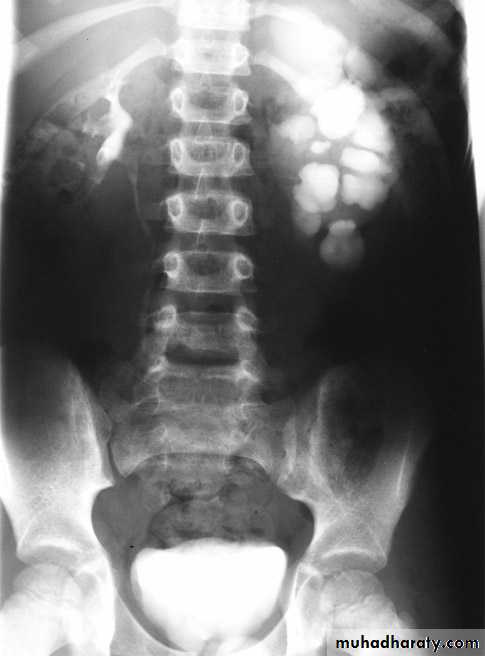

IVU

Large kidney .

Lobulated out-line.

Distortion of pelvi- calyceal system depend on cyst size, number and position.

In advanced cases there is elongation and stretching of minor and major calyces ( spider leg).

In advanced cases IVU shows non-functioning kidney .